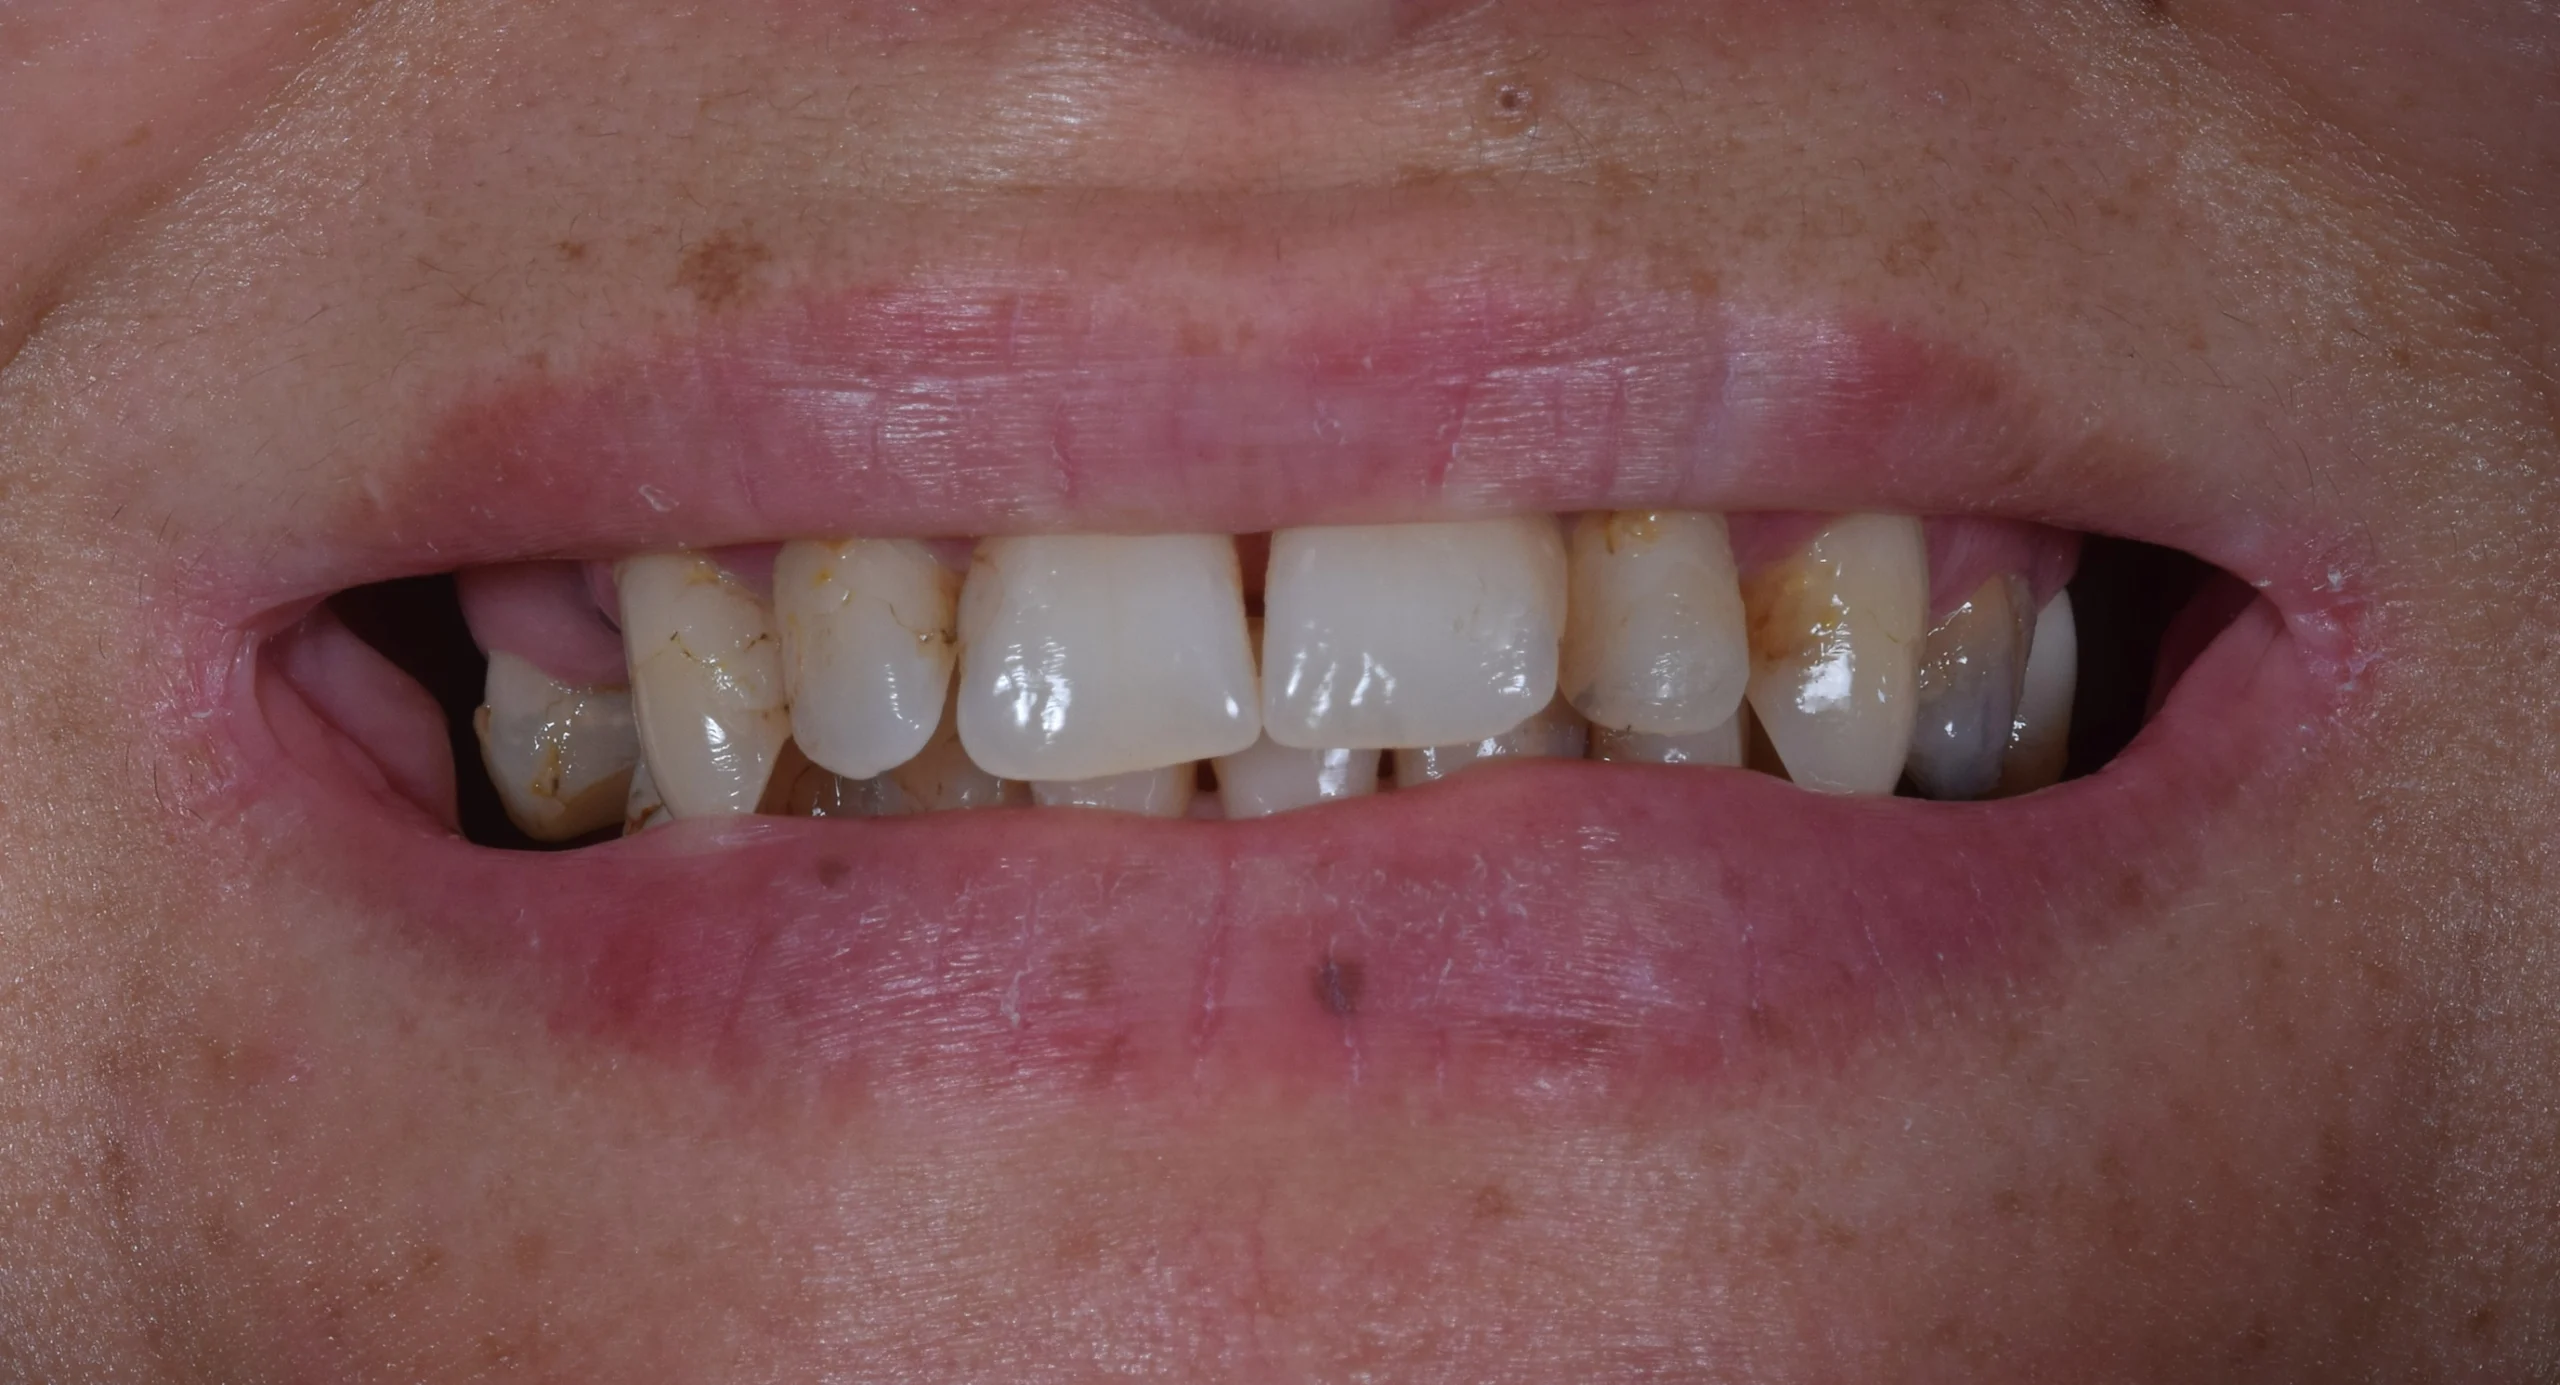

This lovely patient came to our clinic with several missing teeth and a misaligned bite, which significantly affected both her oral health and self-confidence. Everyday activities such as eating and smiling had become a challenge, impacting her overall quality of life.

After a thorough clinical examination and advanced 3D CBCT imaging, we carefully analyzed her condition and created a fully personalized treatment plan.

The solution included a combination of dental implants, crowns, and bridges—designed to restore both function and aesthetics in the most natural way possible.